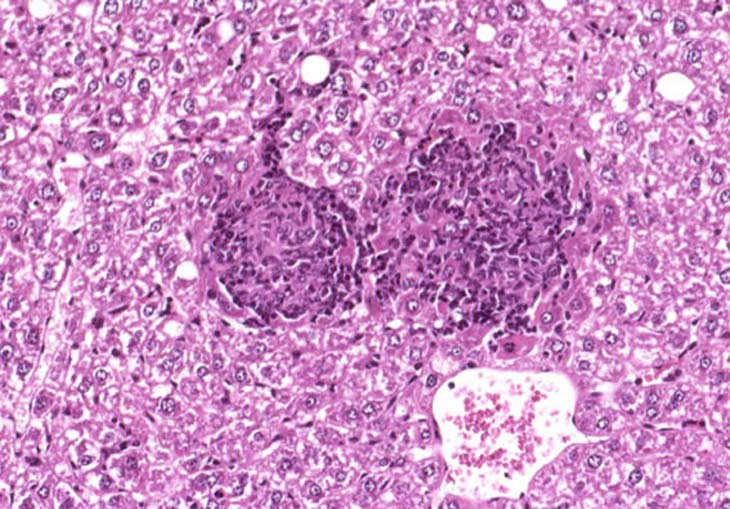

Granuloma in the liver of a B6C3F1 mouse.

Hepatic granulomas in a mouse given dietary tetrachlorvinphos for 2 years. Note that these granulomas are comprised primarily of macrophages and multinucleated giant cells.